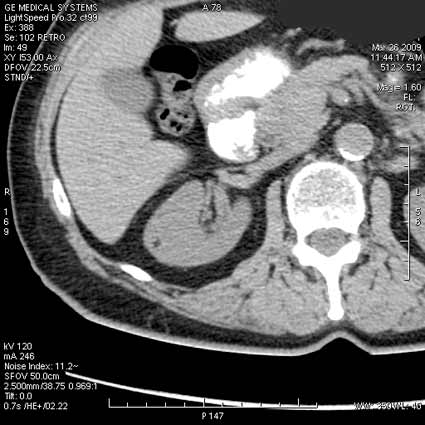

ПО УЗ-семиотике образование соответствует ангиомиолипоме (AML). По правилам в таких случаях необходимо выполнить КТ, доказать преимущественно жировой состав опухоли, затем проводить УЗ-наблюдение.

Согласен. Именно с таким диагнозом (ангиомиолипома) отправил на КТ. Особенностью случая ИМХО является заметный "выход" образования за контур почки (на 2/3 объема).

АНГИОМИОЛИПОМА ПОЧКИ

Ангиомиолипома (почечная гамартома) — опухоль почки, состоящая в различной пропорции из толстостенных сосудов (ангио-), гладких мышц (мио-) и зрелой жировой ткани (липома). Опухоль считается доброкачественной, хотя описано ее экстраренальное распространение (экстраренальная ангиомиолипома), вовлечение региональных лимфатических узлов, а также рецидивы после хирургического удаления [1–5].

При ультрасонографии ангиомиолипома выглядит как округлое образование без капсулы с однородной внутренней эхоструктурой и четкими контурами; эхогенность ее чаще всего равна или чуть выше эхогенности перинефральной клетчатки [7]. Значительно реже эхогенность ангиомиолипом может быть равна эхогенности почечной паренхимы; такие опухоли состоят почти полностью из гладкомышечной ткани [8]. Иногда позади ангиомиолипомы может определяться слабая акустическая тень.

Большинство ангиомиолипом размерами менее 4 см протекают бессимптомно и требуют периодического наблюдения. Жалобы у больных обычно возникают при достижении опухолью размеров 4 см и более [9, 10]. Наиболее грозным осложнением таких образований является их разрыв с кровоизлиянием в периренальное пространство, что может сопровождаться шоком. На потенциально высокий риск разрыва ангиомиолипомы указывает наличие внутриопухолевой псевдоаневризмы, особенно размерами более 5 мм, — такие опухоли требуют превентивного хирургического удаления [11, 12]. При серошкальном ультразвуковом и доплеровском исследованиях псевдоаневризма выглядит как гипо- или анэхогенная структура с высокоскоростным «to-and-fro» («туда и обратно») кровотоком [13].